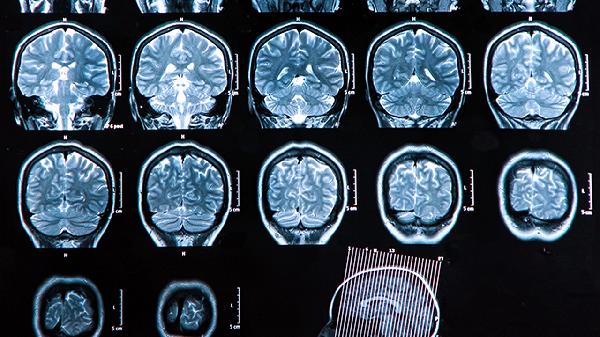

脑溢血可能由高血压、脑血管畸形、动脉瘤、血液病、外伤等因素引起。脑溢血通常表现为头痛、呕吐、意识障碍、肢体无力等症状,严重时可危及生命。建议及时就医,积极配合医生治疗,在医生的指导下服用合适的药物,并做好饮食调理。

高血压是脑溢血最常见的原因,长期高血压会导致脑血管壁变薄、弹性下降,容易破裂出血。高血压引起的脑溢血通常起病急骤,患者可能出现剧烈头痛、恶心呕吐、意识模糊等症状。治疗高血压需要长期服用降压药物,如硝苯地平控释片、缬沙坦胶囊、氢氯噻嗪片等,同时要控制饮食、减少钠盐摄入、保持规律作息。